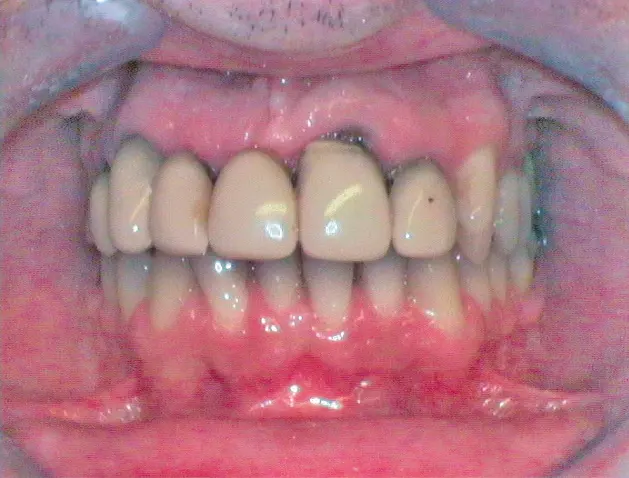

Nach Freilegung der Implantate regio 026,027 im Februar 2020, bei der auch die Implantation regio 037 (T3, Zimmer Biomet Dental, 4,0 mm x 13,0 mm) vorgenommen wurde (Abb. 32 OPG nach Freilegung), erfolgte im März nach Abformung mit offenem Löffel (open tray technique) und Gesichtsbogenregistrat die prothetische Versorgung mittels CAD/CAM gefräster Abutments (Dentaltechnik Hessel und Lutgen, Trier) und transversal verschraubter, verblockter VMK-Kronen (Abb. 33-36). Die Freilegung und Versorgung des Implantates 037 ist zusammen mit der Entfernung des Zahnes 38 für Juli 2020 geplant.